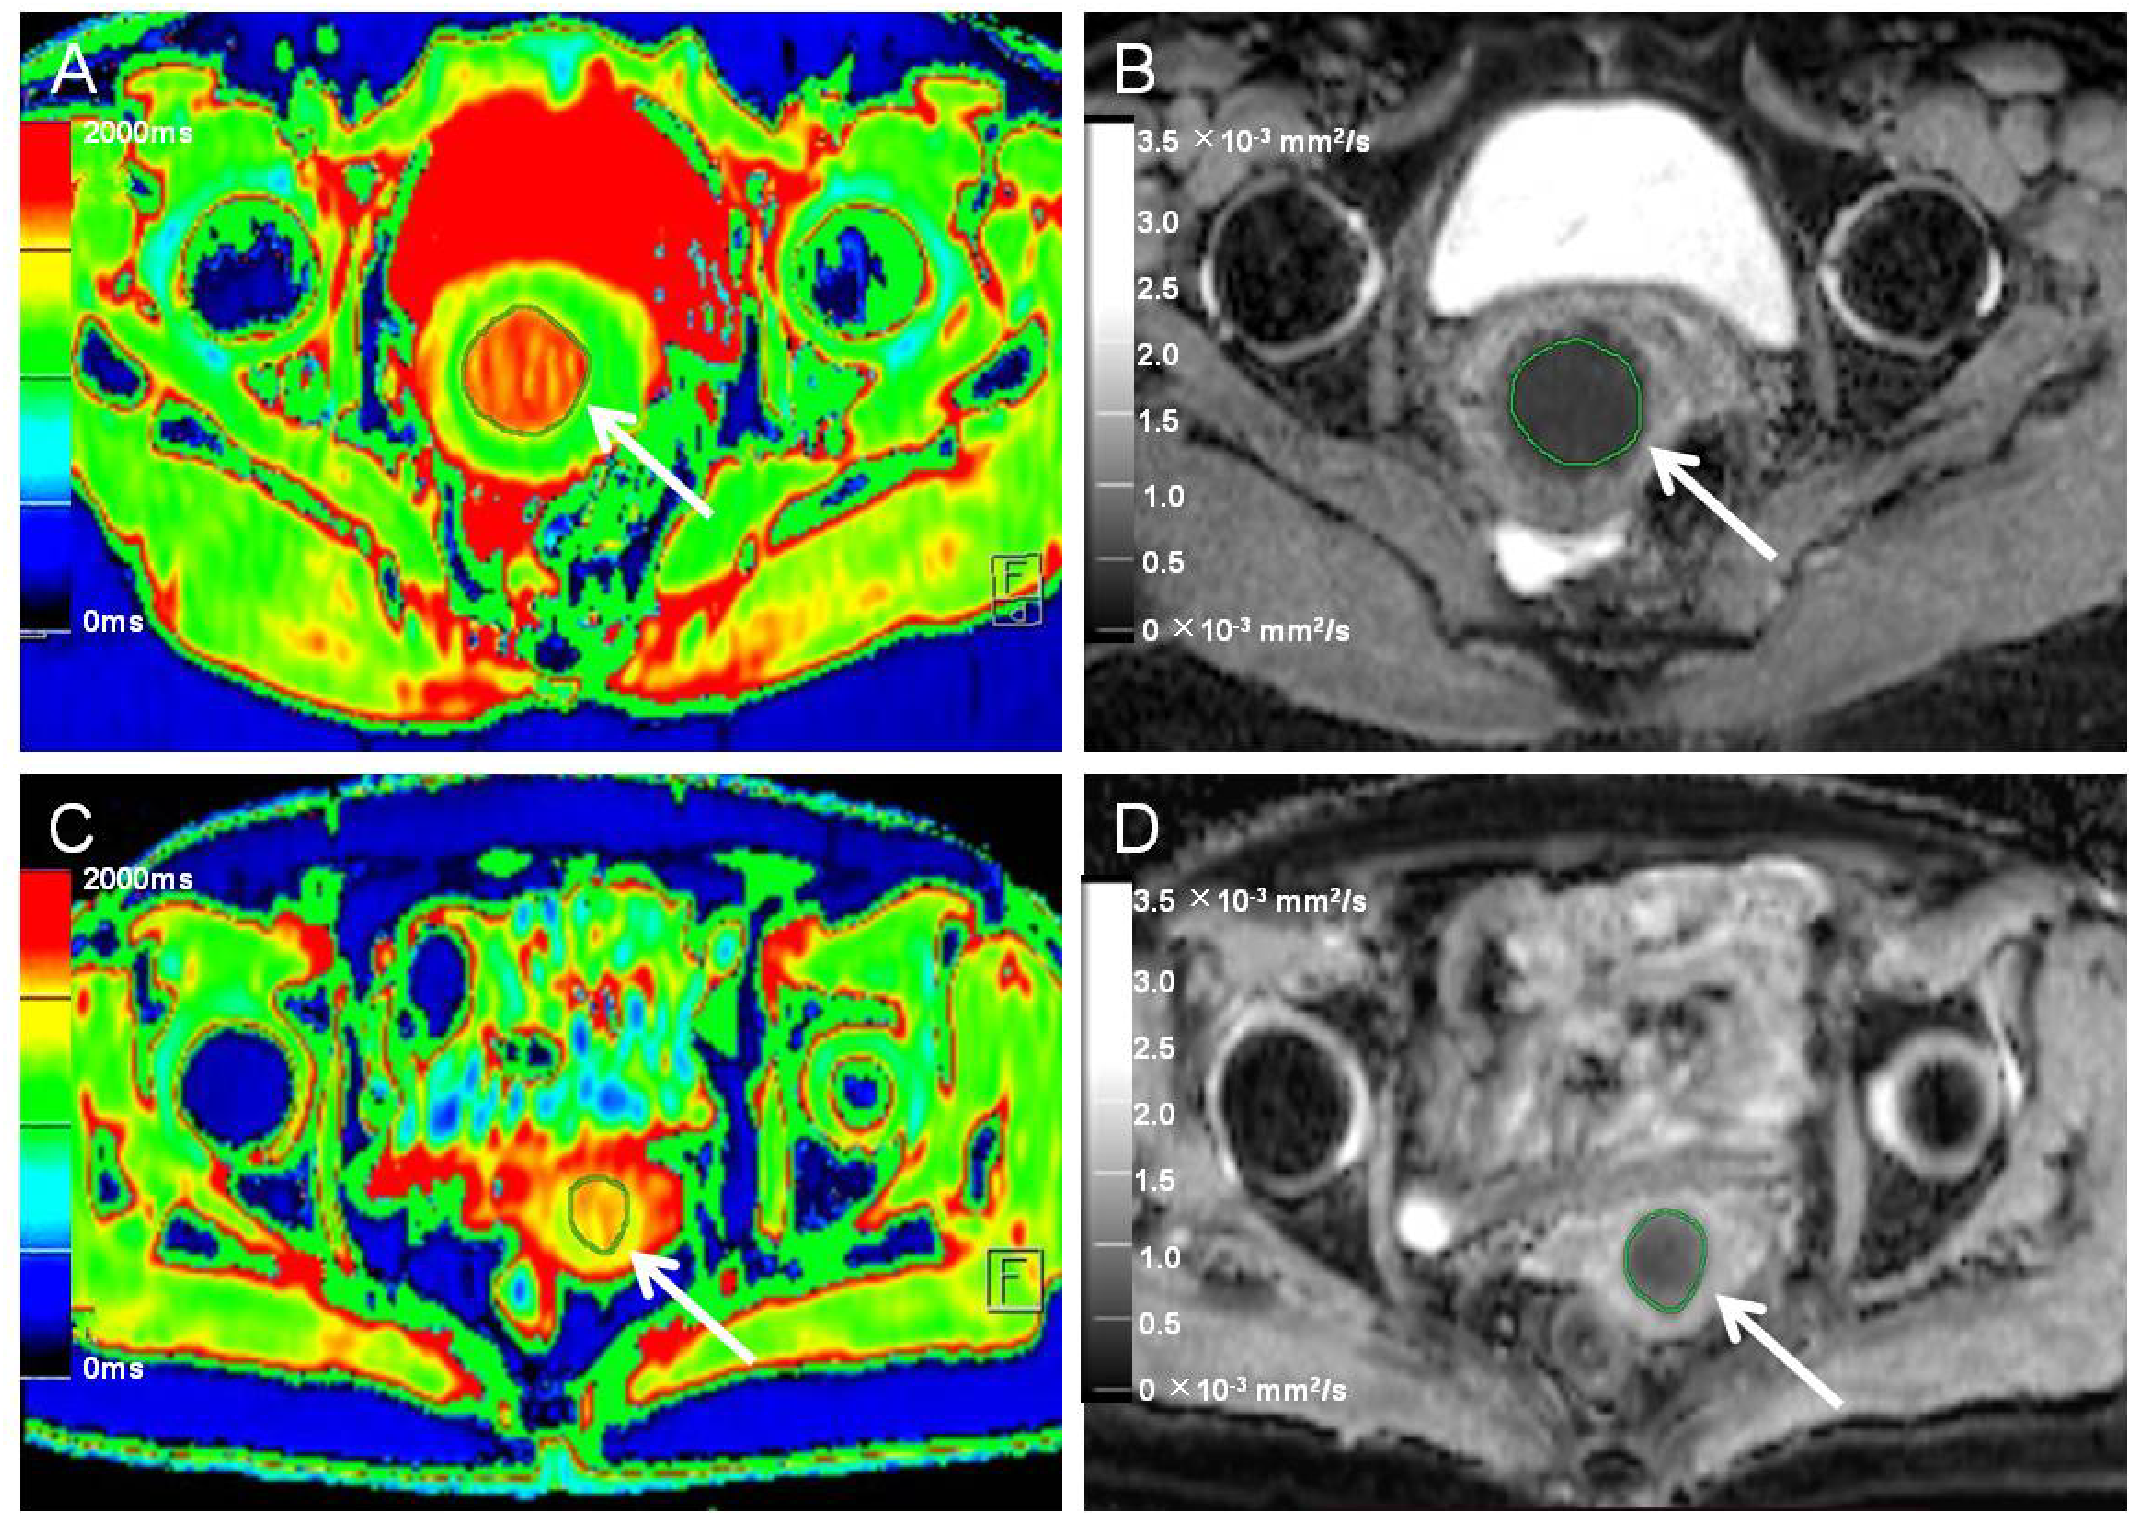

Figure 2

Native T1 mapping and apparent diffusion coefficient (ADC) images of recurrent and nonrecurrent cervical cancer (CC) in the surgical group. (A, B) A 45-year-old patient with recurrence during the follow-up period. (A) Axial T1 mapping pseudo-color map and (B) axial ADC image. The native T1 and ADC values were 1619.20 ms and 0.68 × 10−3 mm2/s, respectively. (C, D) A 61-year-old patient without recurrence during the follow-up period. (C) Axial T1 mapping pseudo-color map and (D) axial ADC image. The native T1 and ADC values were 1480.19 ms and 0.82 × 10−3 mm2/s, respectively. The white arrows in A-D indicate the locations of the lesions.